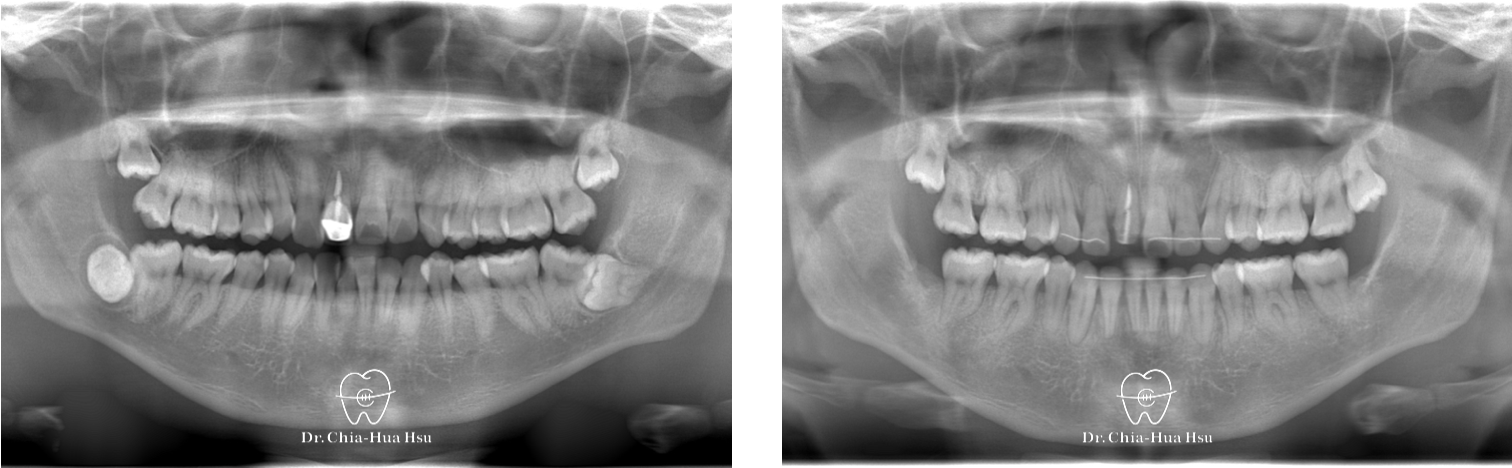

前牙錯咬、齒列擁擠

• 問題分析:患者是標準的骨骼一類咬合(Skeletal Class I)伴隨齒列擁擠以及前牙錯咬。

• 治療方式:拔除四顆小臼齒,使用傳統金屬矯正器將牙齒排列整齊、咬合緊閉。

治療前

治療後